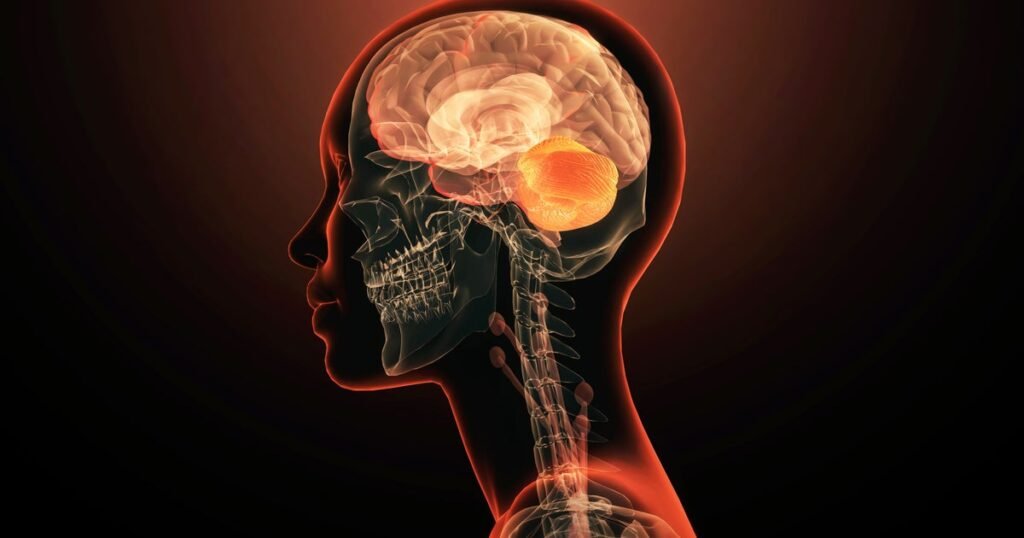

The brain is the most complex organ in the body. It regulates everything from body temperature to memories to breathing and generates thousands of thoughts every day.